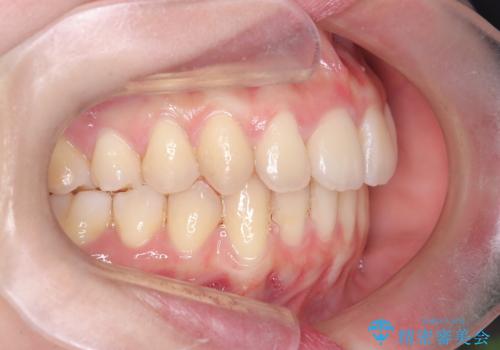

- 前歯の突出を主訴に来院されました。

アンカースクリューとインビザラインを用いて遠心移動を行うことでできる限り前歯を下げて叢生の改善を行いました。

遠心移動を行う際は、患者様にゴムの使用をお願いしております。